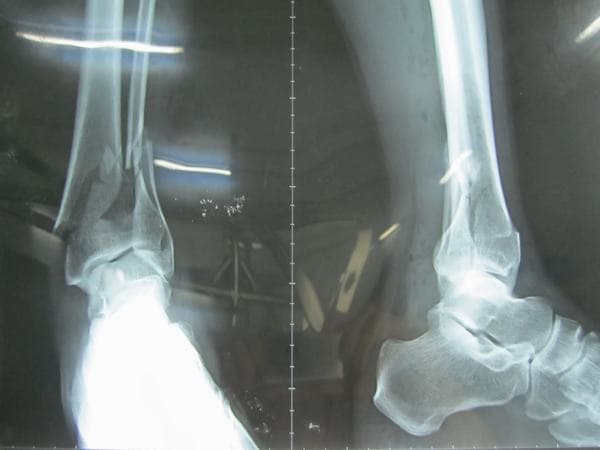

Gãy xương mác cẳng chân bao lâu thì lành và cách chăm sóc?

Xương mác là xương nhỏ nên rất dễ bị gãy. Tuy nhiên gãy xương mác không quá nguy hiểm và có thể lành lại. Vậy gãy xương mác cẳng chân bao lâu thì lành?

Gãy xương mác cẳng chân bao lâu thì lành? Theo các chuyên gia y tế, có rất nhiều nguyên nhân gây gãy xương mác, chủ yếu là va chạm mạnh do tai nạn giao thông, té ngã từ trên cao xuống hoặc thực hiện các động tác vặn xoay cơ mạnh quá. Tình trạng này hay gặp ở những vận động viên, những người luyện tập các môn thể thao như trượt ván, trượt tuyết.

Gãy xương mác có thể gặp ở mọi đối tượng, lứa tuổi với mức độ gãy và nguyên nhân gãy khác nhau, ảnh hưởng nghiêm trọng tới khả năng vận động, đi lại.